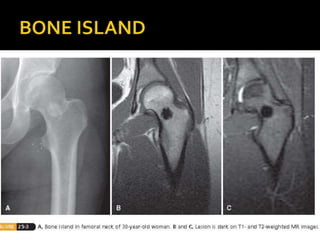

 A.K.A “Enostoses”

 Benign lesions of cancellous bone

 Common in adults, sites – Pelvis, femur

 Usually asymptomatic

 Imaging studies - Small round area of

increased density in cancellous bone with

radiating spicules at periphery.

 Mature bone with thickened trabeculae that

merge with normal bone at the periphery

 Treatment – Observation.